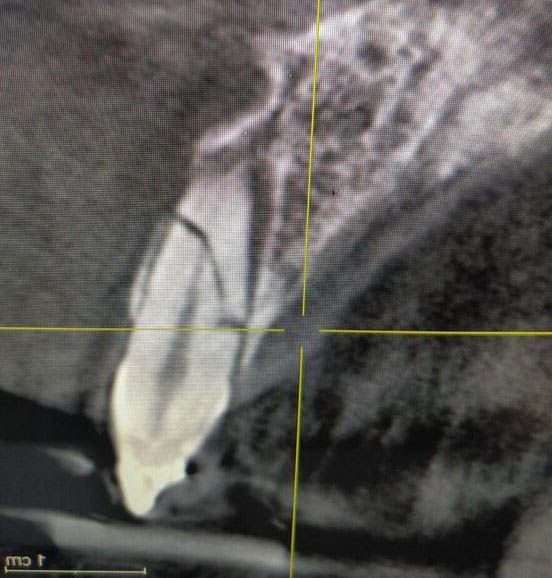

Initial radiographic situation, which shows the fracture of the element 1.1.

Cone Beam at 6 months: the bone thickening of the buccal bony wall, essential for long-term soft tissue maintenance, is evident.